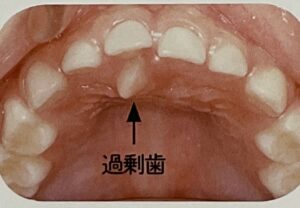

また、つばを飲み込む度に歯のすき間に舌を突き出す癖があると、

舌の力で歯がおされて前歯が開き開咬というかみ合わせになるとも言われています。